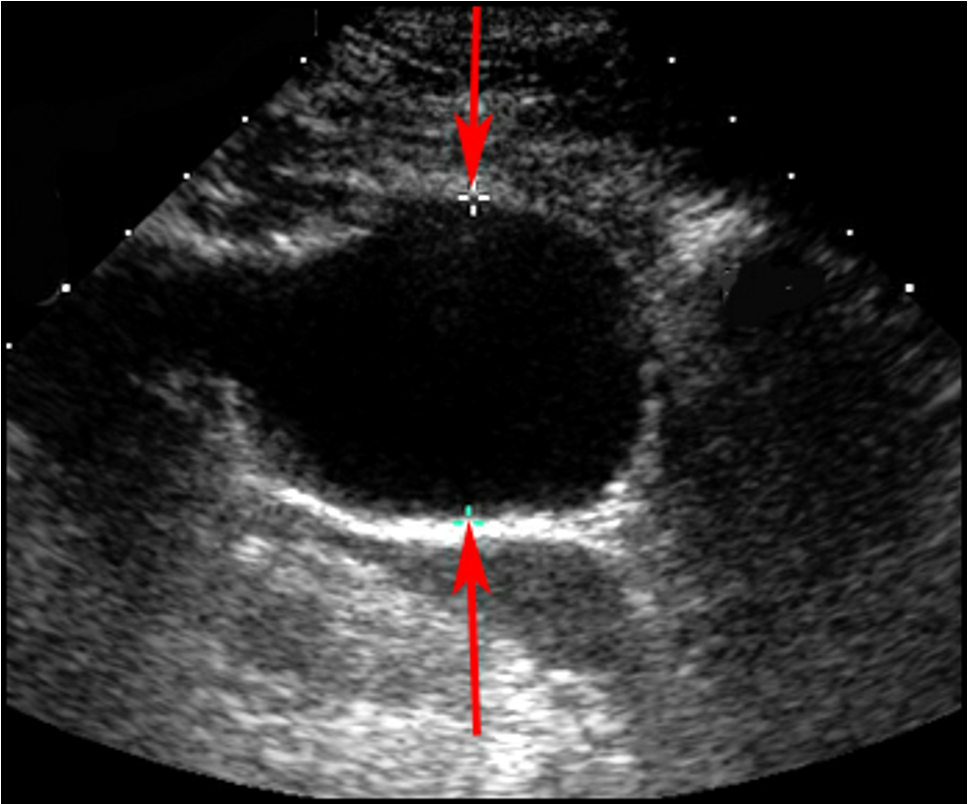

What does this ultrasound refer to

aortic aneurysm